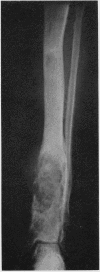

An example of chondrosarcoma developing in a patient with Ollier's disease is described. Necropsy showed an unusual pattern of multiple metastases including several within the cranial cavity.

Images in this article